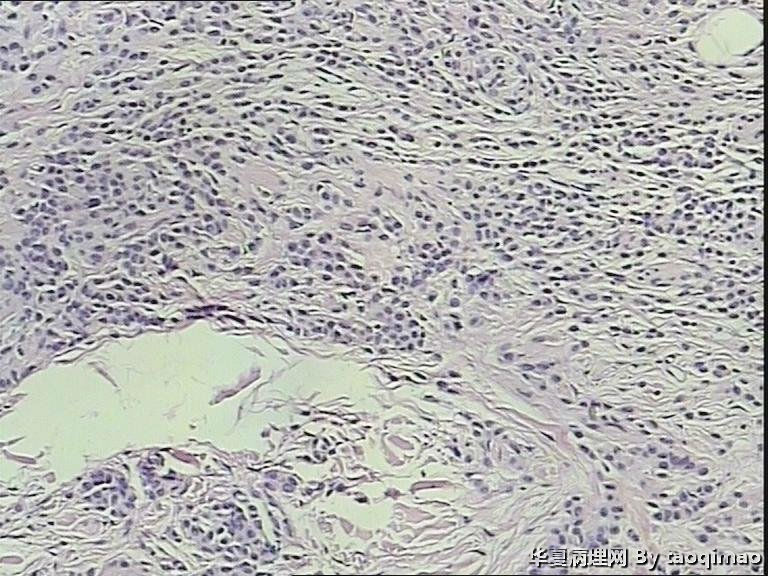

两例头皮肿物有差别么

34岁女,头皮肿物,带皮组织一块1x1,皮瓣上可见一灰白结节大小0.6x0.6,皮瓣大小1x0.4 面灰白质软。

门诊患者这一例没有其它更多信息

第一:皮内痣 第二:皮内痣并表皮囊肿

这个患者女,24岁,右颞部头皮肿物 24年,带皮的组织一块1.7x1x1,突出于皮肤表面,灰白色肿物,剖面实性灰白,请各位老师给帮忙诊断一下,这两个病例是同一个诊断么

没差别

皮内痣。

都考虑皮内痣。

但第一例处于退化期了,当然,这没必要写到报告上。

都要考虑皮内痣。实在有差别就是第2例上有表皮囊肿,容易伴发。

皮内痣,第2例伴表皮囊肿,1处于退化期,倒是该学学

第二例合并的有个小的表皮样囊肿,或说粟丘疹。

灰白色,我想是由于有的皮内痣本身没有太多色素吧,不少皮内痣是皮色的。你的俩病例,片子里都没啥见到色素,应该可以解释了吧。

头皮皮内痣常呈皮赘样,质软有蒂,很多时候退化后呈正常肤色,切片中常有成熟的脂肪细胞,临床很容易误诊,诊断皮内痣应该没有问题的!